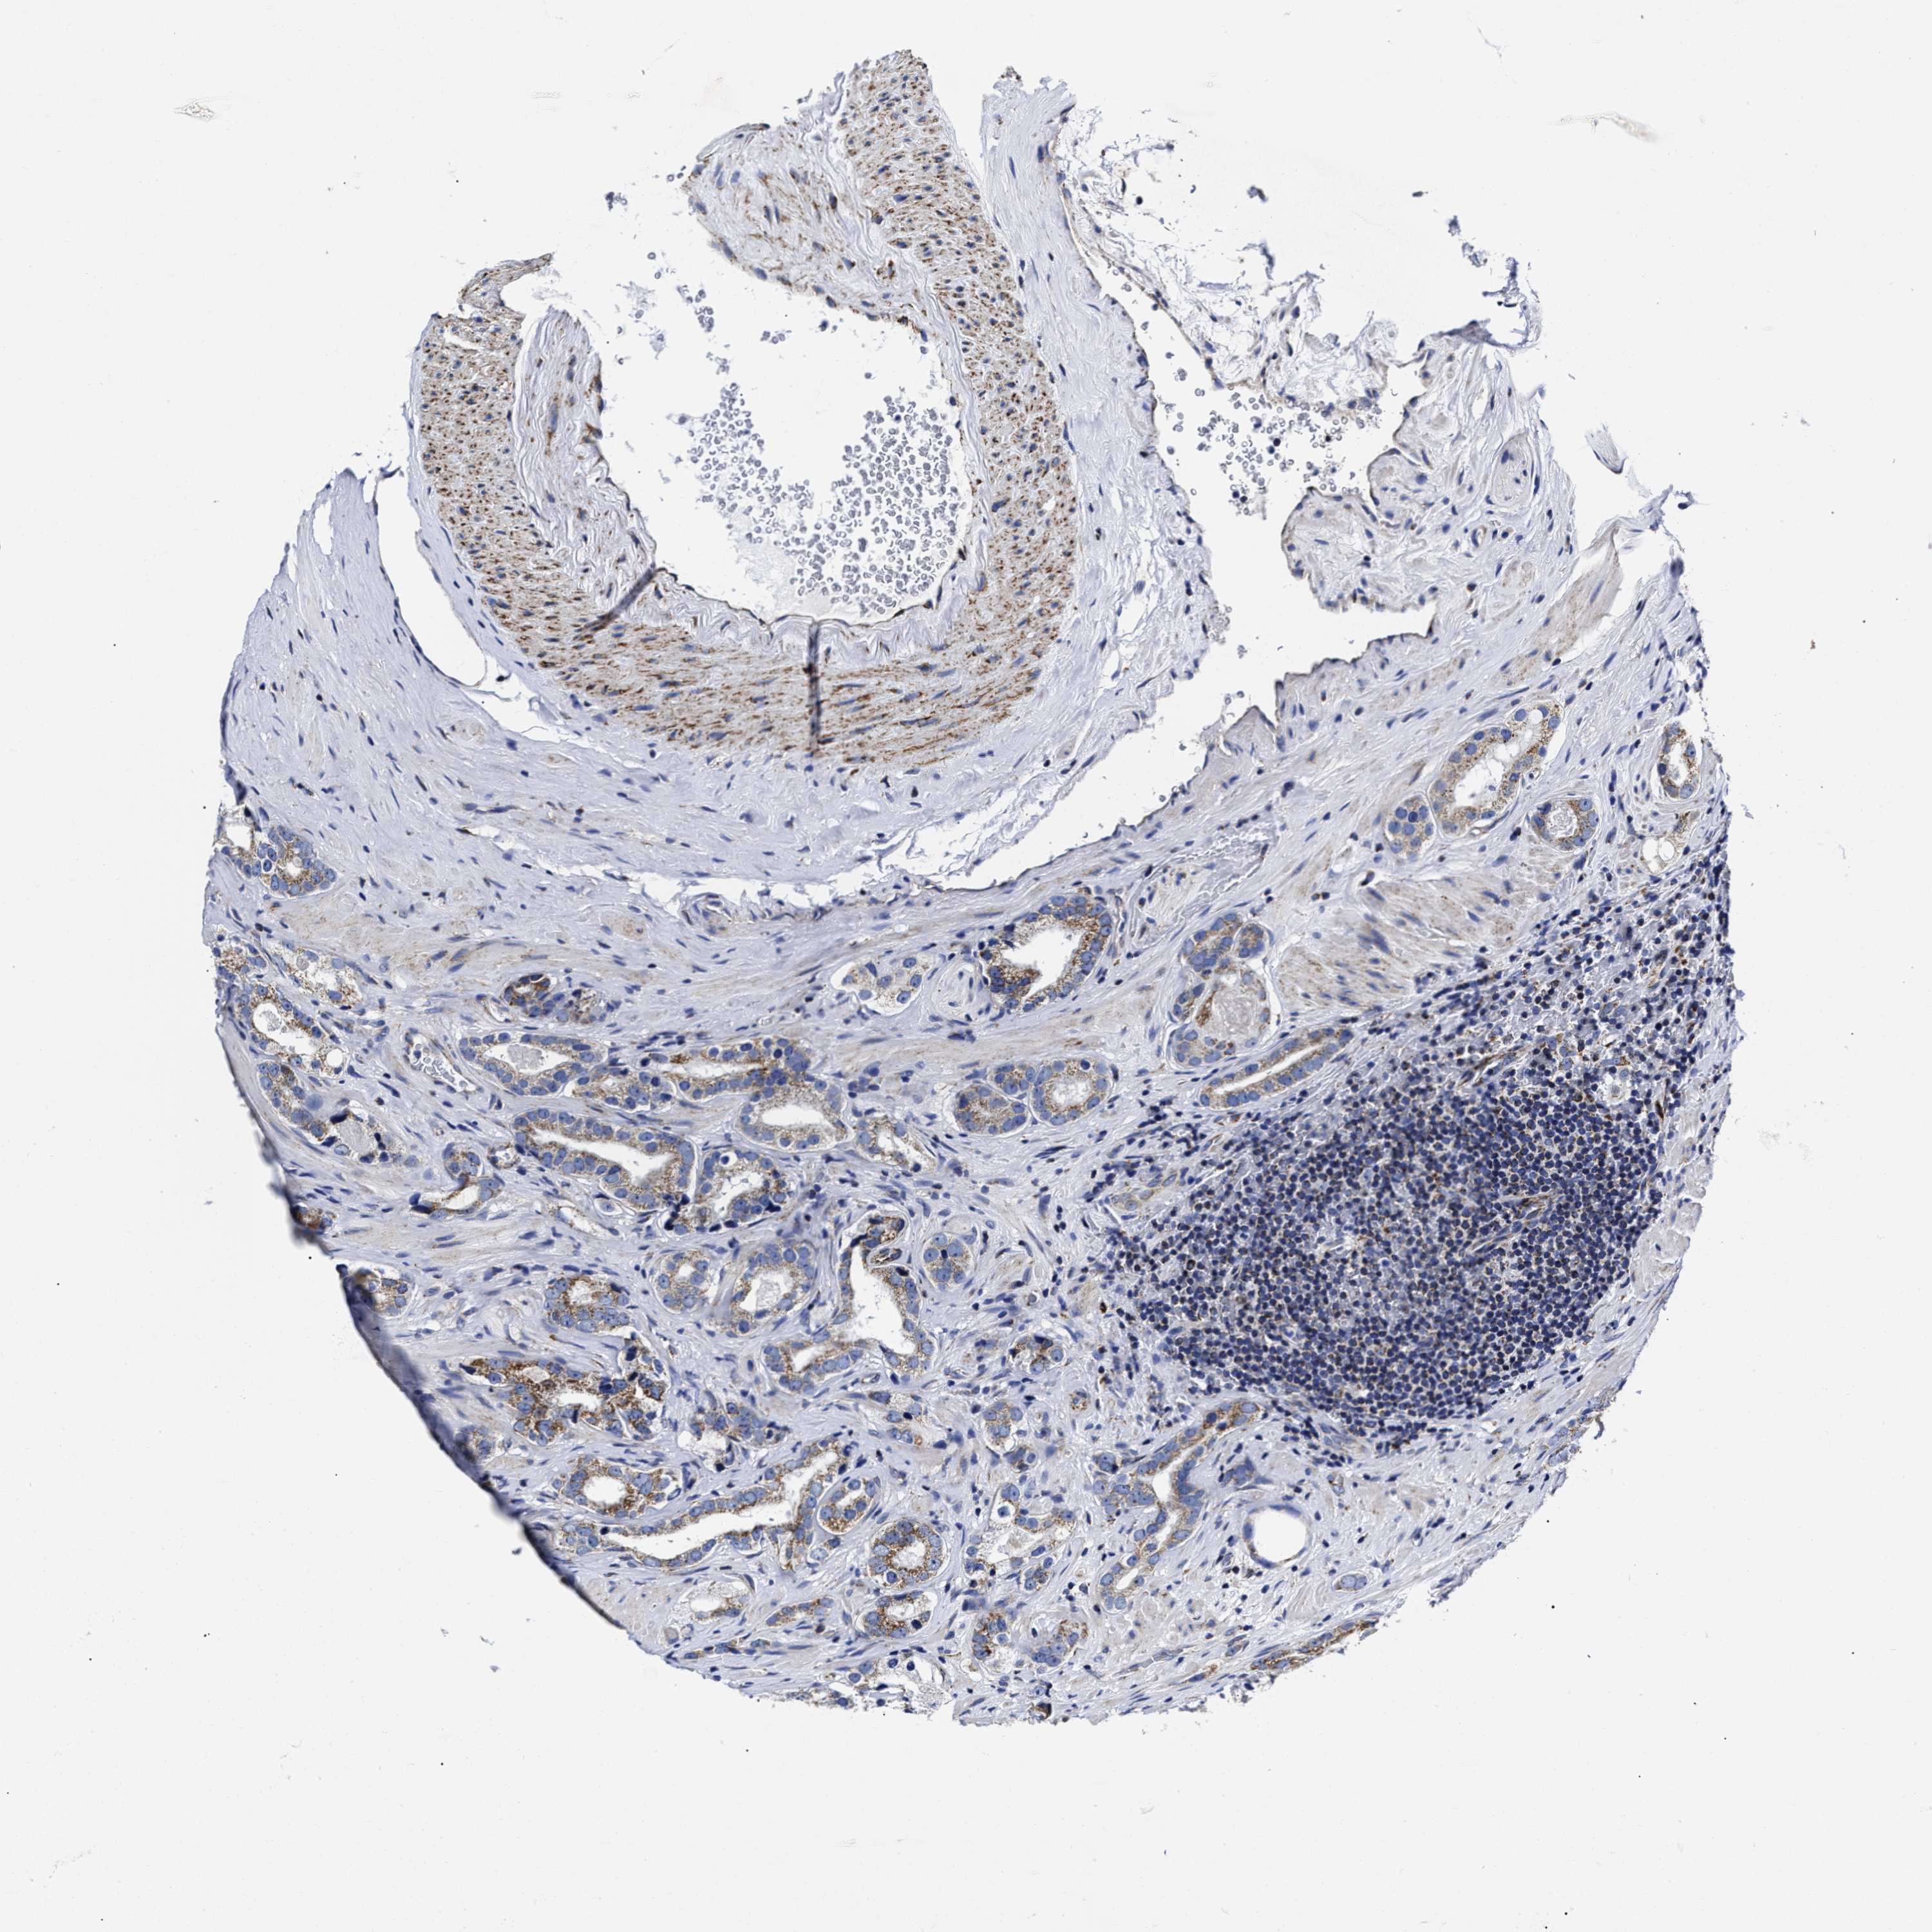

PROSTATE CANCER - Protein expressioni

A mouse-over function shows sample information and annotation data. Click on an image to view it in a full screen mode. Samples can be filtered based on level of antibody staining by selecting one or several of the following categories: high, medium, low and not detected. The assay and annotation is described here.

Note that samples used for immunohistochemistry by the Human Protein Atlas do not correspond to samples in the TCGA dataset.

Antibody stainingi

Antibody staining in the annotated cell types in the current human tissue is reported as not detected, low, medium, or high, based on conventional immunohistochemistry profiling in selected tissues. This score is based on the combination of the staining intensity and fraction of stained cells.

Each image is clickable and will lead to virtual microscopy that enables deeper exploration of all samples and also displays staining intensity scores, fraction scores and subcellular localization as well as patient and tissue information for each sample.

Antibody HPA020961

Antibody HPA059109

Staining

High

Medium

Low

Not detected

Intensity

Strong

Moderate

Weak

Negative

Quantity

>75%

75%-25%

<25%

None

Location

Nuclear

Cytoplasmic/membranous

Cytoplasmic/membranous,nuclear

Adenocarcinoma, High grade

Adenocarcinoma, Low grade